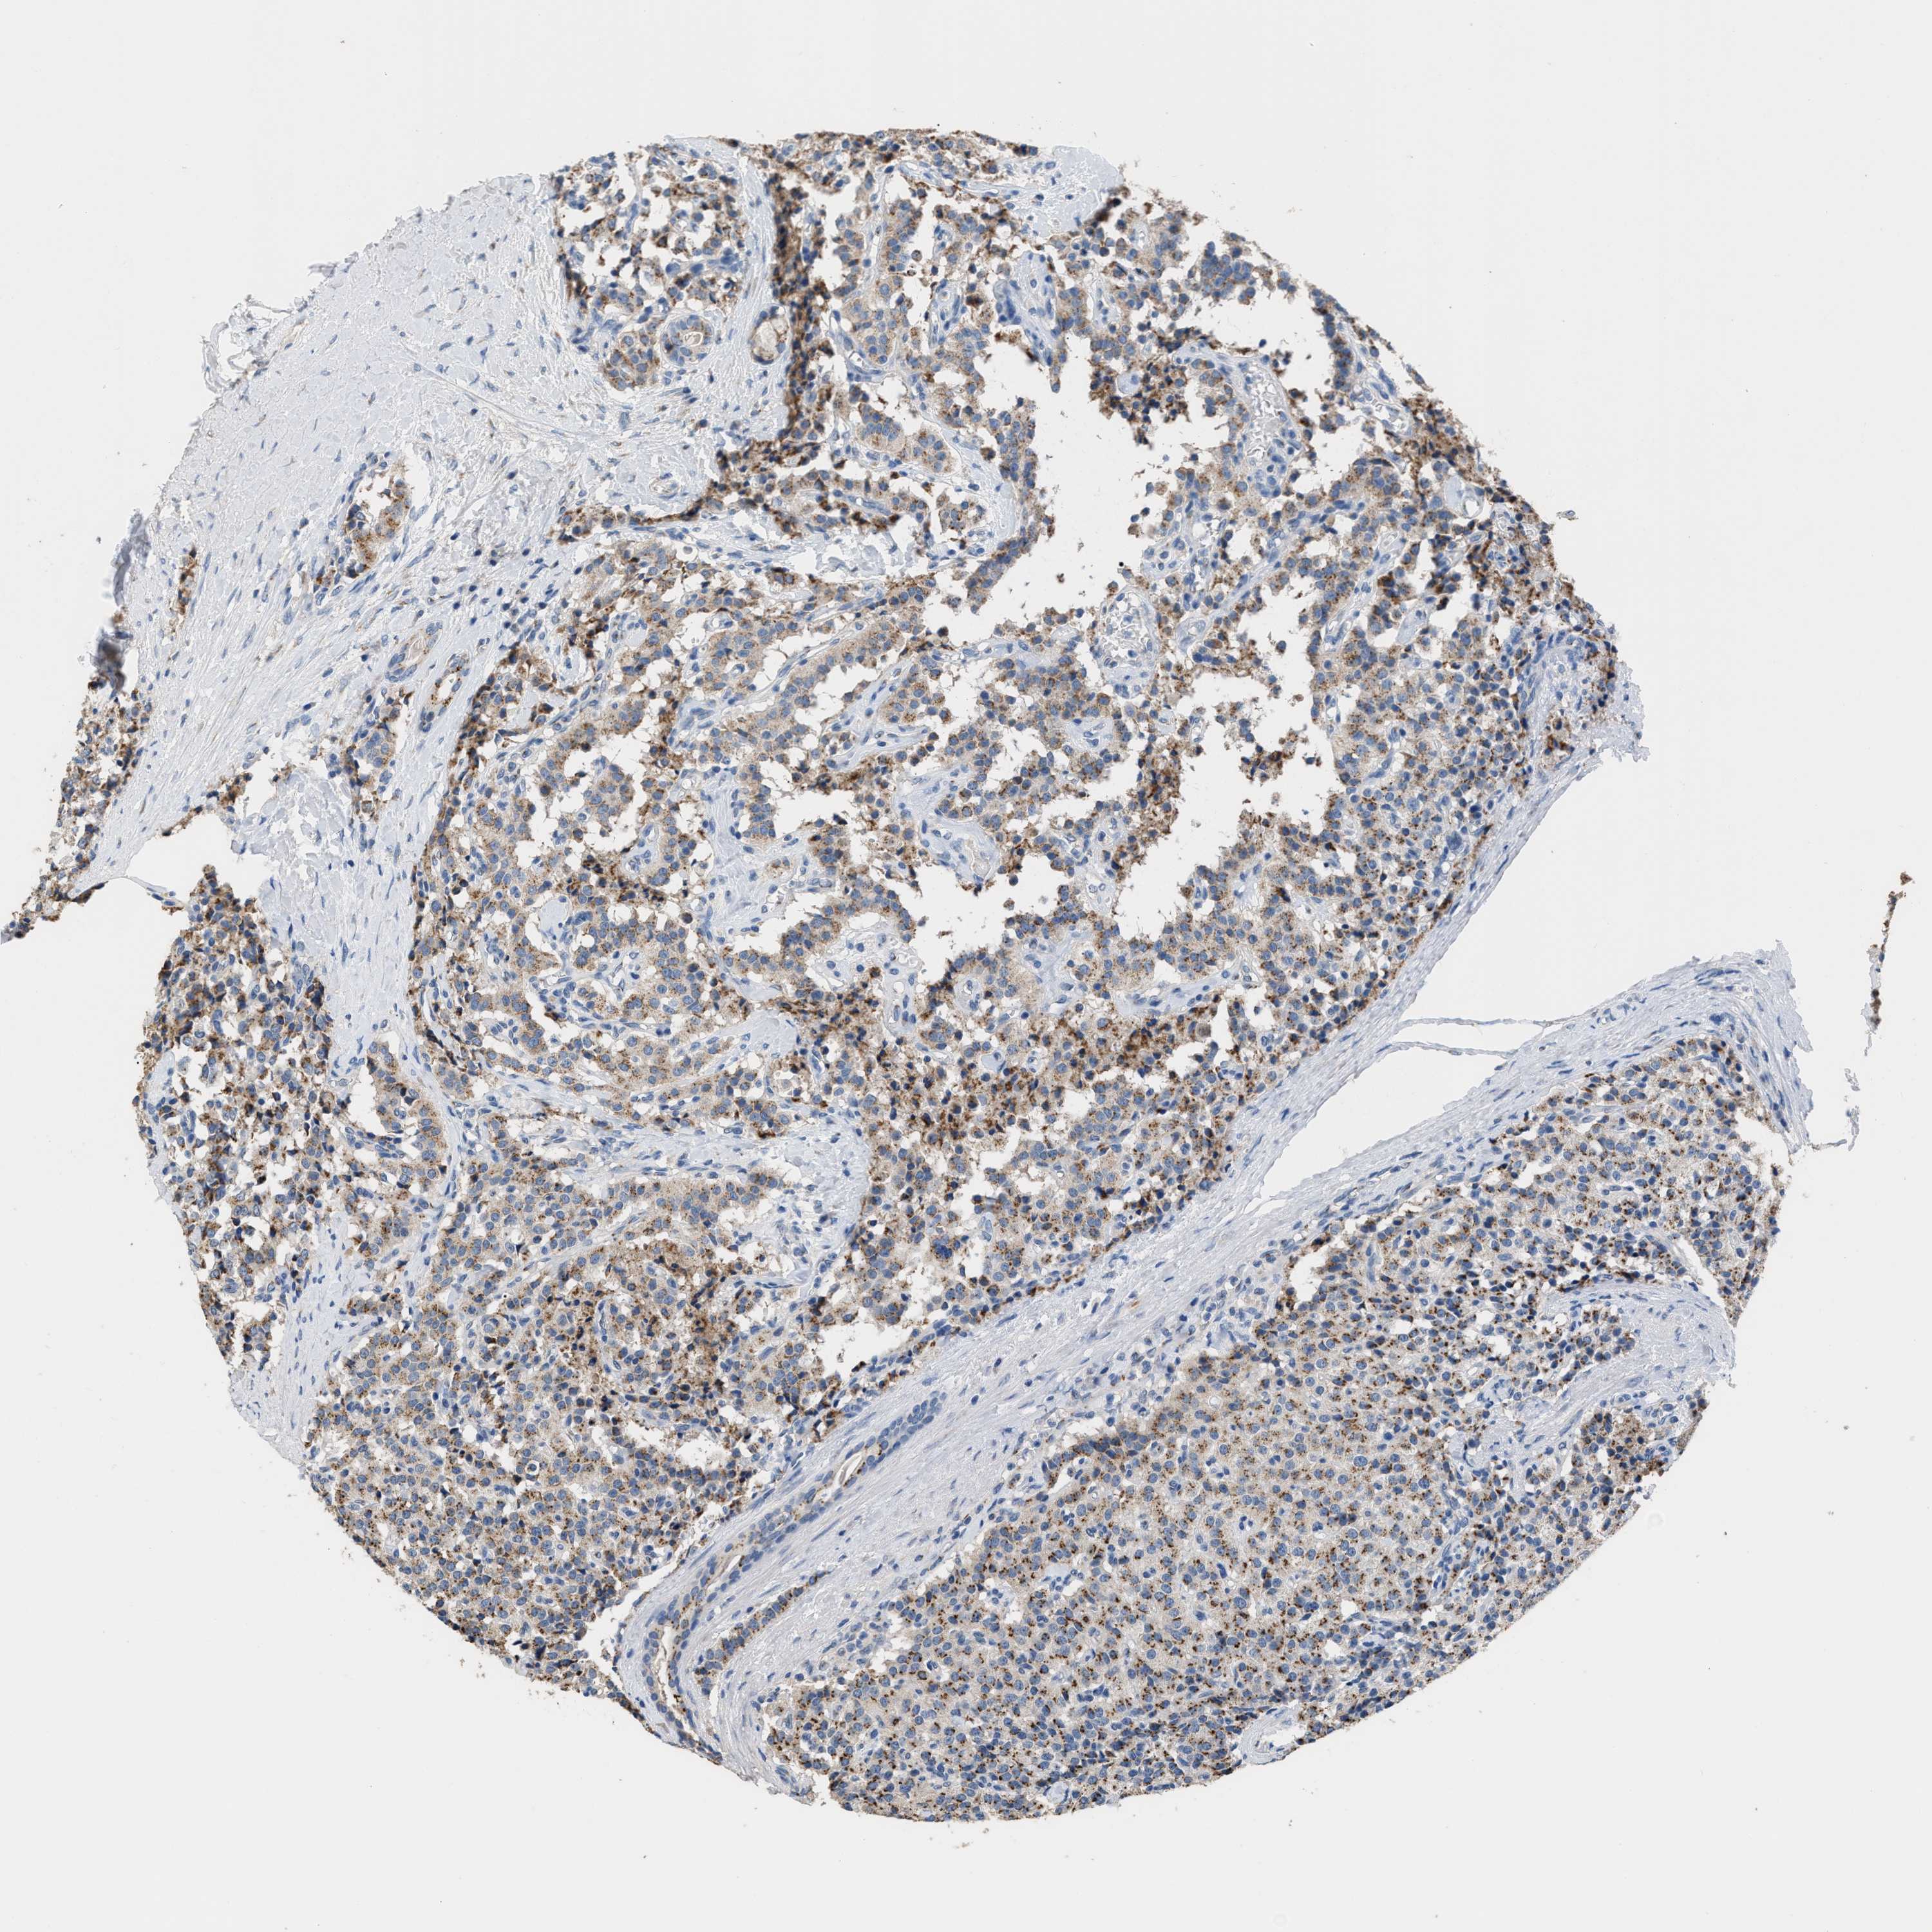

CARCINOID - Protein expressioni

A mouse-over function shows sample information and annotation data. Click on an image to view it in a full screen mode. Samples can be filtered based on level of antibody staining by selecting one or several of the following categories: high, medium, low and not detected. The assay and annotation is described here.

Each image is clickable and will lead to virtual microscopy that enables deeper exploration of all samples and also displays staining intensity scores, fraction scores and subcellular localization as well as patient and tissue information for each sample.

Antibody HPA010638

Staining

High

Medium

Low

Not detected

Intensity

Strong

Moderate

Weak

Negative

Quantity

>75%

75%-25%

<25%

None

Location

Nuclear

Cytoplasmic/membranous

Cytoplasmic/membranous,nuclear

Carcinoid, malignant, NOS

Carcinoma, NOS